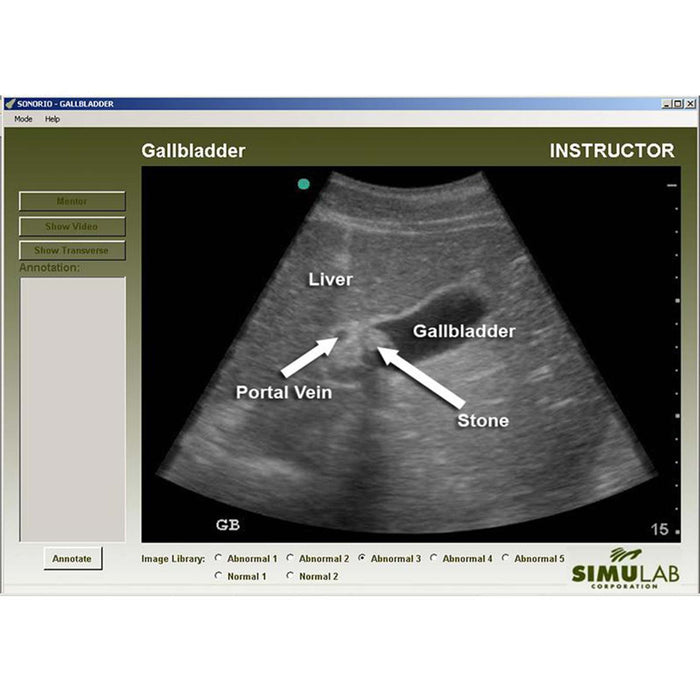

The training system offers an extensive image and video library with an option of six software modules (sold separately). Each module provides up to seven clinical cases presenting normal or abnormal findings, allowing the instructors to mimic various pathologies in emergent or critical care settings.

Within the software modules, instructors can pre-program pathologies allowing users to assess, locate, and then diagnose the patient while visualizing the complete thoracic and abdominal region.

- Images and videos are of actual patients - both normal and abnormal

- Each module includes an instructor (enable visual instruction with mentor mode to discuss pathology and diagnoses) and student mode (randomly selects patient to build diagnosis and decision-making skills)

- Mentor mode allows users to activate onscreen guidance identifying the anatomy and pathology of digital images

- Understand and diagnose disease states using patient images, videos, and ultrasound acquisition on the body form